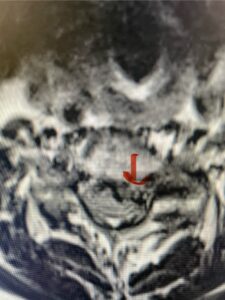

This 61-year-old female with a history of severe osteoporosis and a prior history of a laminectomy from l2-S1 with an L5-S1 instrumented fusion, presents with progressive low back pain and right lower extremity radiculopathy. MRI revealed a grade 1 L2-3 spondylolisthesis with severe stenosis mainly from severe right L2-3 facet joint hypertrophy which was compressing the right L3 descending nerve root. (Fig. 1). She had failed conservative management consisting of physical therapy and pain management with epidurals. She underwent an L1-3 revision laminectomy where we had to dissect a plane underneath the inferior aspect of the L2 lamina. We performed an instrumented fusion at L2-3 with special hydroxyapatite-coated screws to improve fixation to surrounding bone given here severe osteoporosis (Fig. 2) This worked out well and the patient had an uneventful recovery with relief of her leg pain.

Figures 1a: Sagittal and axial T2-weighted lumbar MRIs demonstrating a grade 1 L2-3 spondylolisthesis (red arrow) with severe stenosis secondary to right L2-3 facet hypertrophy (red arrow).

Fig 1b: Note the left L2-3 facet joint (blue arrow) is normal in size compared to the right (red arrow)